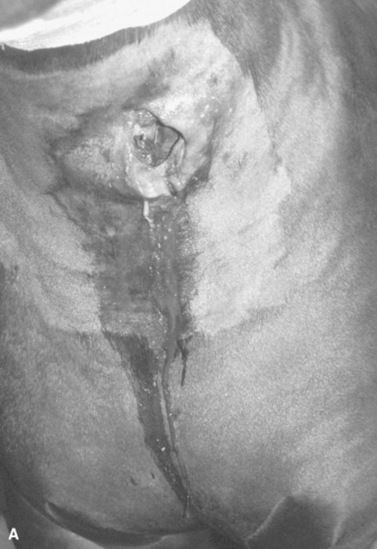

Survey radiography is generally helpful to evaluate the cervical esophagus for evidence of rupture as well as to evaluate the abdomen. Esophageal ruptures secondary to an obstruction or vigorous placement of a nasogastric tube result in a small volume of gas that tracks just dorsal to the trachea (Fig. 32-2). This can be confused with a tracheal laceration; however, with tracheal lacerations generally the gas accumulation will surround the trachea and the volume of gas within the subcutaneous tissues and the cranial mediastinum will be severe. In addition, esophageal obstructions, also called choke, can sometimes be identified on survey radiographs depending on the material that is causing the obstruction and the amount of air or contrast medium that is able to surround the structure (Fig. 32-3). Although the nature of the obstruction cannot be determined, the extent of the abnormality can sometimes be identified.